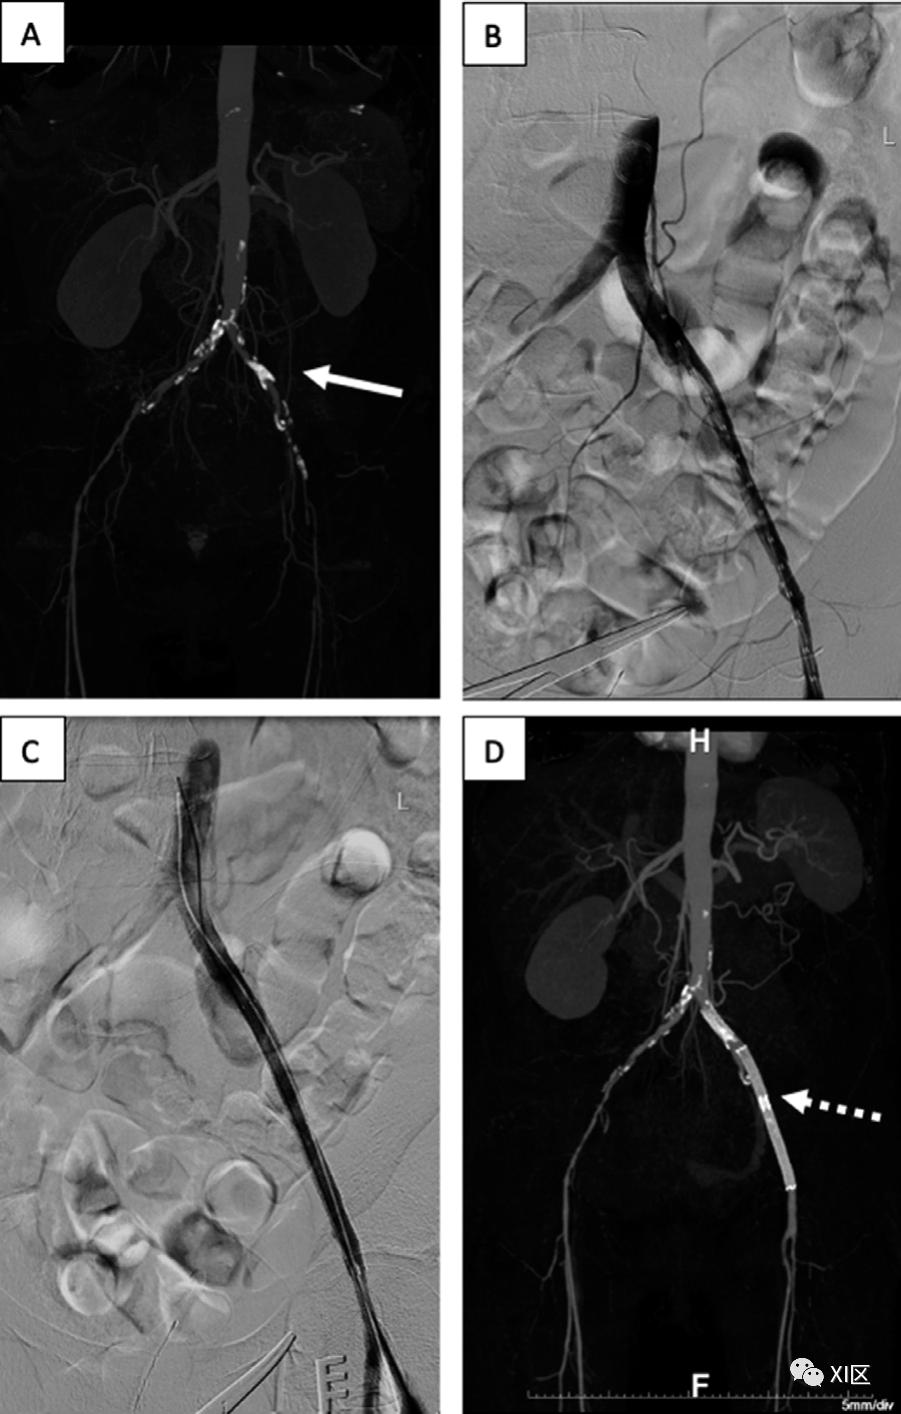

图6 59岁女性严重左腿缺血。A)冠状位上的最大密度投影CTA图像显示左髂外动脉钙化(箭头),导致严重严重狭窄/闭塞和流出减少。B)植入支架前的术中血管造影显示,通过左髂外动脉闭塞的血流减少。C)支架置入后的术中血管造影显示,与B相比,血流增加。D)冠状位上的最大密度投影CTA图像显示左侧髂外动脉支架(虚线箭头)和改善的血管流出。其他决定性的关键治疗细节包括CFA或PFA的参与、SFA闭塞的特征(弥漫性或局灶性,近端或远端),以及对作为外周旁路移植或膝下干预的潜在目标血管的跖动脉和足动脉的评估。特别是腘动脉的受累,由于其位置和流动性,使得该血管的治疗具有挑战性,因此在计划进行血管内或手术干预时需要仔细关注。根据病变的长度和狭窄程度,可以按照跨TASC标准进行分类,这是一个解剖学分类系统,为最佳血管再通策略(血管内与手术)的治疗决策提供指导(图7)。为了准确使用TASC标准,需要报告每个病变的特征,而不仅仅是最严重的病变。